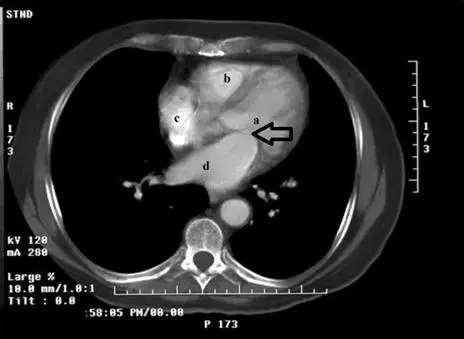

下圖 a、b、c、d所指最可能之解剖位置分別為何?

本題考查胸部軸位(axial)電腦斷層掃描(computed tomography, CT)影像上四個心腔的辨識,包含左心室(left ventricle, LV)、右心室(right ventricle, RV)、左心房(left atrium, LA)及右心房(right atrium, RA)的解剖位置關係。這是醫事放射師必須熟練掌握的基礎心臟解剖判讀能力。

本題圖片為增強型軸位 CT(contrast-enhanced axial CT)掃描,掃描層面位於心臟中段水平。影像依標準放射科判讀慣例顯示,左側(L)標記在影像右方,右側(R)標記在影像左方。

四個標記位置分析:

- 標記 a:位於影像中左側,心臟厚壁結構,有箭號指向,周圍可見心肌壁較厚,形態呈橢圓/圓形,為左心室(left ventricle)。左心室壁厚度約為右心室的三倍,是最容易辨識的結構特徵。

- 標記 b:位於影像上方偏左,體積較大、位於前方的腔室,形態為三角形/月牙形,壁薄,為右心室(right ventricle)。右心室位於心臟最前方,圍繞左心室前方延伸。

- 標記 c:位於影像右側(患者左側),呈卵圓形,為右心房(right atrium)。右心房位於心臟右外側緣,上下腔靜脈在此匯入。

- 標記 d: